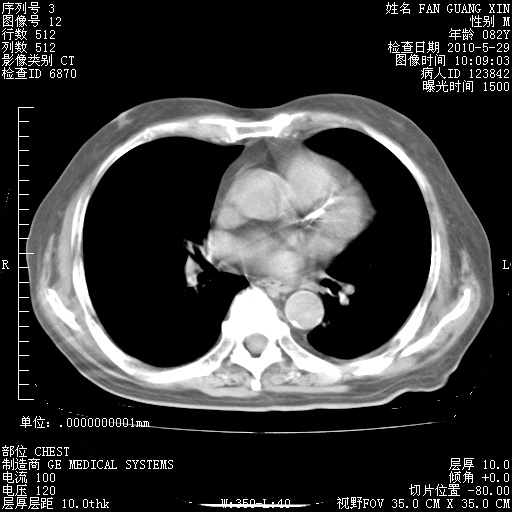

发表于 2010-5-19 19:23

还需要哪些辅助检查?我们医院排除真菌感染没有任何检验方法,胸片好像能够排除肺部真菌感染。

补充:ENA化验全部阴性。免疫五项(IgG、IgA、IgM、C3、C4)只有C4略高。